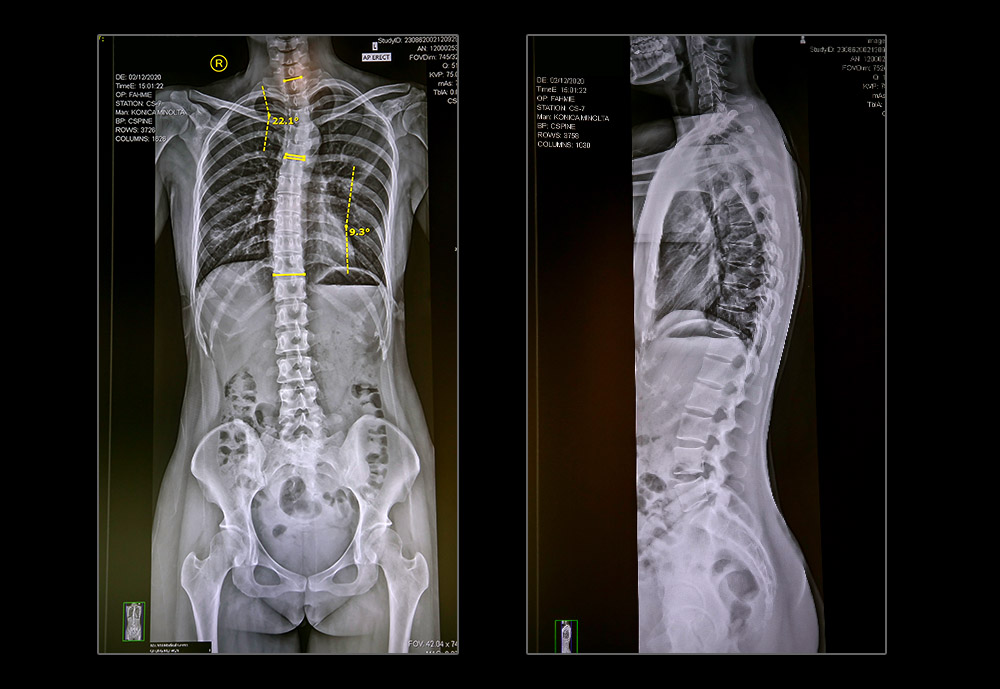

Spinal Imaging

In many cases, spinal images are critical in confirming an accurate diagnosis. Like a blueprint of an engineering drawing, it shows us the construction of your spinal design and allow us to plan a specific course of action.

Should you already have a set of spinal images, we encourage you to bring them along.